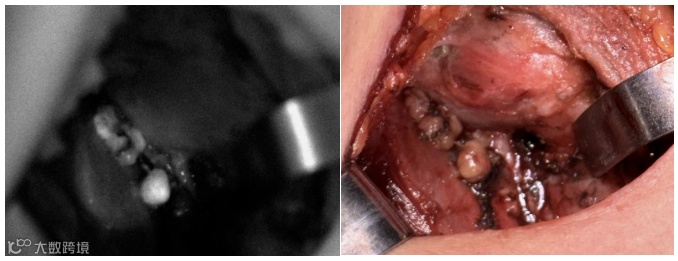

我们通过技术创新实现了荧光摄像系统,用于临床甲状腺手术中辅助医生实现甲状旁腺的鉴别,识别率高达95%以上;

我们以自研的超高灵敏度荧光成像技术结合先进的高精度投影定位技术以及超清的图像融合技术,在甲状旁腺识别领域中开创性的引入了实时便捷的光学标记识别方法,极大的提高了手术效率,降低手术风险。

同时产品可与吲哚菁绿造影剂联合使用,对皮下淋巴管、血管进行定位,对相关组织的血流灌注进行评估。